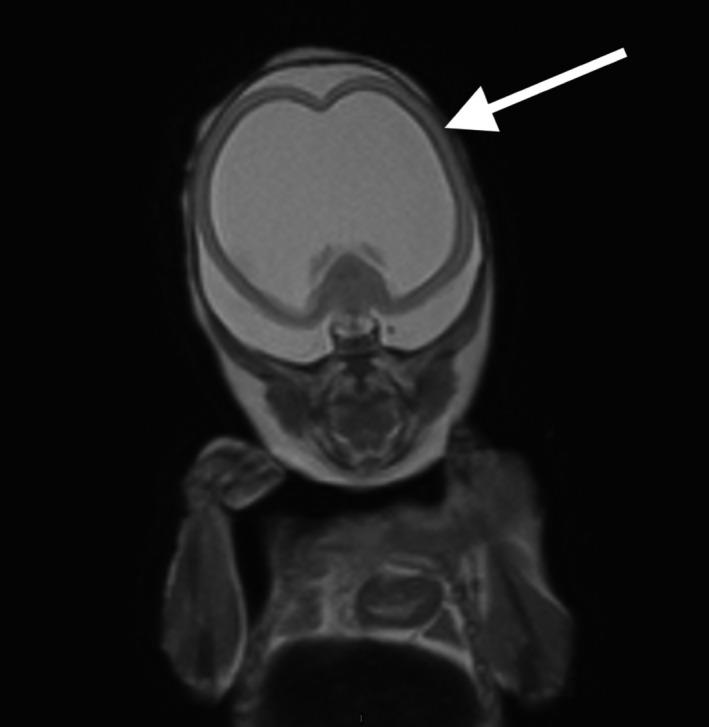

中孕期因畸形而终止妊娠胎儿的死后磁共振成像与尸检比较

Postmortem magnetic resonance imaging vs autopsy of second trimester fetuses terminated due to anomalies.

Our aim was to investigate the accuracy of postmortem fetal magnetic resonance imaging (MRI) compared with fetal autopsy in second trimester pregnancies terminated due to fetal anomalies. A secondary aim was to compare the MRI evaluations of two senior radiologists.

MATERIAL AND METHODS

This was a prospective study including 34 fetuses from pregnancies terminated in the second trimester due to fetal anomalies. All women accepted a postmortem MRI and an autopsy of the fetus. Two senior radiologists performed independent evaluations of the MRI images. A senior pathologist performed the fetal autopsies. The degree of concordance between the MRI evaluations and the autopsy reports was estimated as well as the consensus between the radiologists.

RESULTS

Thirty-four fetuses were evaluated. Sixteen cases were associated with the central nervous system (CNS), five were musculoskeletal, one cardiovascular, one was associated with the urinary tract, and 11 cases had miscellaneous anomalies such as chromosomal aberrations, infections and syndromes. In the 16 cases related to the CNS, both radiologists reported all or some, including the most clinically significant anomalies in 15 (94%; CI 70%-100%) cases. In the 18 non-CNS cases, both radiologists reported all or some, including the most clinically significant anomalies in six (33%; CI 5%-85%) cases. In 21 cases (62%; CI 44%-78%), both radiologists held opinions that were consistent with the autopsy reports. The degree of agreement between the radiologists was high, with a Cohen's Kappa of 0.87.

CONCLUSIONS

Postmortem fetal MRI can replace autopsy for second trimester fetuses with CNS anomalies. For non-CNS anomalies, the concordance is lower but postmortem MRI can still be of value when autopsy is not an option.

我们的目的是研究与因胎儿畸形而终止妊娠的胎儿中孕期尸检相比,胎儿磁共振成像(MRI)的准确性。次要目的是比较两位资深放射科医生的 MRI 评估结果。

材料与方法

这是一项前瞻性研究,纳入了 34 例因胎儿畸形而在中孕期终止妊娠的胎儿。所有女性均接受了胎儿死后 MRI 和胎儿尸检。两位资深放射科医生对 MRI 图像进行了独立评估。一位资深病理学家进行了胎儿尸检。MRI 评估与尸检报告的一致性程度以及放射科医生之间的共识程度均进行了评估。

结果

共评估了 34 例胎儿。16 例与中枢神经系统(CNS)有关,5 例与肌肉骨骼系统有关,1 例与心血管系统有关,1 例与泌尿系统有关,11 例有多种异常,如染色体异常、感染和综合征。在与 CNS 相关的 16 例病例中,两位放射科医生均报告了所有或部分病例,包括 15 例(94%;CI 70%-100%)最具临床意义的异常。在 18 例非 CNS 病例中,两位放射科医生均报告了所有或部分病例,包括 6 例(33%;CI 5%-85%)最具临床意义的异常。在 21 例(62%;CI 44%-78%)病例中,两位放射科医生的意见与尸检报告一致。两位放射科医生的意见一致性较高,Cohen's Kappa 值为 0.87。

结论

对于中枢神经系统畸形的中孕期胎儿,死后胎儿 MRI 可替代尸检。对于非 CNS 异常,一致性较低,但当无法进行尸检时,死后 MRI 仍然具有价值。